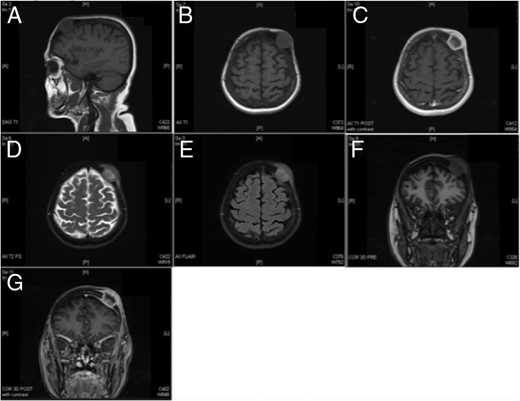

The patient, a 69-year-old white female, was referred by her primary care provider to a plastic surgeon at United Hospital Center for treatment of what was believed to be a soft-tissue mass of the left forehead (frontoparietal region) (Fig. 1). The mass had increased in size for the prior 2–3 months and resulted in a radiating pain down the left side of the face. The mass was non-mobile and tender to touch. Prior to this referral, the patient was relatively healthy with a past medical history significant for arthritis, depression and hypertension. Her surgical history was positive for tonsillectomy and partial hysterectomy. Her social history is significant for a 60-pack-year smoking history (1.5 packs/day for 40 years). The soft tissue mass had been managed conservatively for presumptive dermatological infection (subcutaneous/sebaceous cyst) with a 10-day course of levofloxacin 500 mg tablets taken once daily. The tablets, however, provided no symptomatic relief. Imaging (computed tomography (CT)) of the maxillofacial area and brain without contrast was obtained in addition to plain films of the skull. These images revealed a lytic lesion of the skull in the left frontopartietal region (Fig. 2). The patient was referred to the oncology department for further workup.

CT soft tissue demonstrating the presence of a lytic lesion in the left frontopartietal region. (A) Axial cut, (B) coronal cut and (C) sagittal cut.